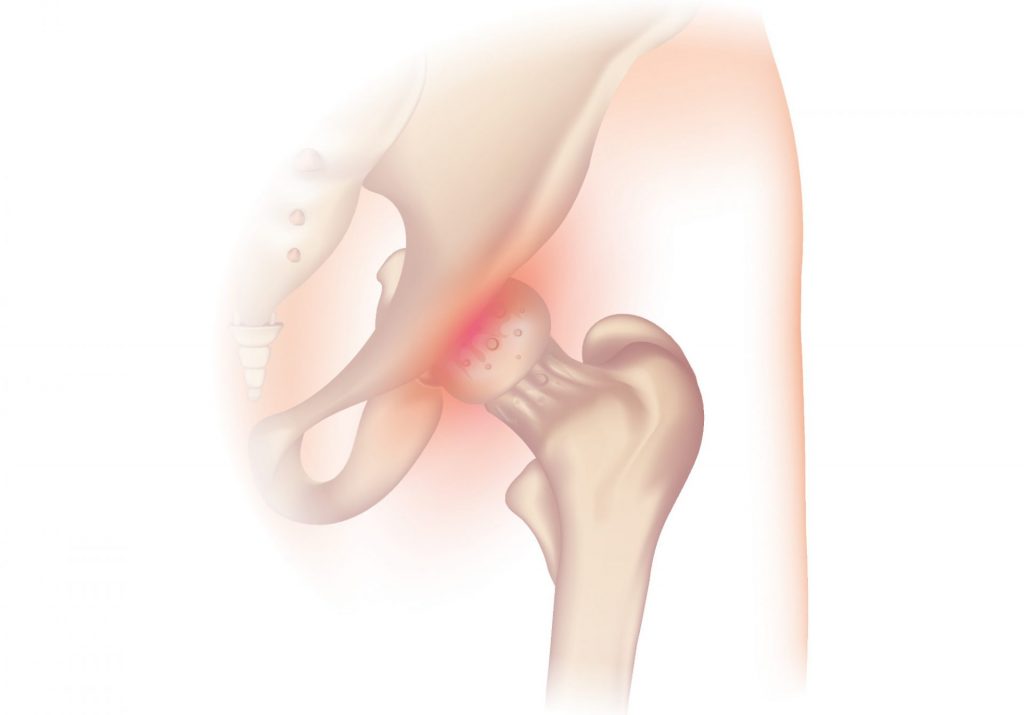

Definition og anatomi af hoften

Før du går i detaljer, er det vigtigt at forstå hoftens anatomi for bedre at forstå, hvor slidgigt i dette led kommer fra.

Hoften er et af de største led i kroppen. Det forbinder bækkenbenet (via et hulrum kaldet acetabulum) og lårbenshovedet (den øverste del af lårbenet).

De knogleagtige overflader af lårbenshovedet og acetabulum er dækket af ledbrusk, et stof, der giver stødabsorbering og bevægelse.

Overfladen af leddet er også dækket af en tynd hinde kaldet synovia. I en sund hofte producerer synovium en lille mængde tilstrækkelig væske, der smører brusken og letter bevægelsen.

I nogle situationer revner brusken i hofteleddet gradvist og slides væk. Som følge heraf reduceres dens dæmpningskapacitet. Ledrummet mellem knoglerne mindskes, hvilket kan få knoglerne i bækkenet og lårbenet til at gnide mod hinanden.

Dette fænomen svarer til slidgigt i hoften. For at kompensere for tabet af brusk kan beskadigede knogler begynde at danne knoglefremspring (kaldet osteofytter). Dette kan forårsage betændelse og smerte.

Denne diagnose (såvel som tilstedeværelsen af osteofytter) kan stilles med et simpelt røntgenbillede af hoften.